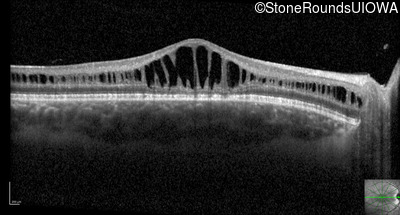

Optical Coherence Tomography - Right - 20/63 -2

Exemplar / OCT Stack

Optical Coherence Tomography - Left - 20/50 -2